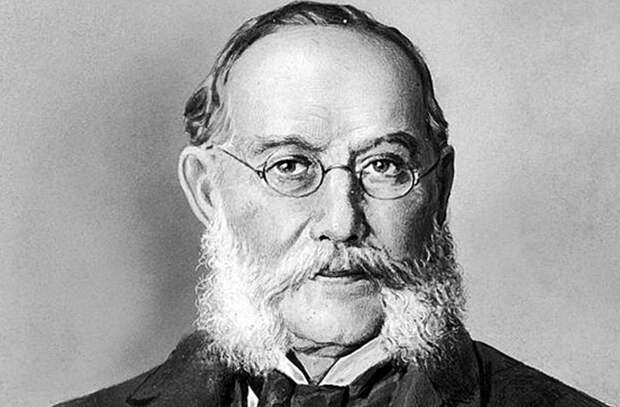

Карлос Финлей, открывший, что желтая лихорадка передается, попадая в кровоток, обычно при укусах комаров

Будучи практикантом в одной из пенсильванских больниц и решив опровергнуть версии о заразности болезни, Фирф был крайне изобретателен в доказательных методах. Закапывая рвотные массы, полученные от больных, себе в глаза, поливая ими разрезы, сделанные на теле и даже выпивая их в большом количестве, Фирф так и не заразился. Однако он глубоко заблуждался в своей теории. Все дело в том, что желтая лихорадка передается при попадании в кровоток, обычно при укусах комаров. К сожалению, эта информация впервые появилась спустя 60 лет после смерти Стаббинса Фирфа — в работах кубинского врача Карлоса Финлея, а экспериментально была подтверждена лишь в 1900 году.